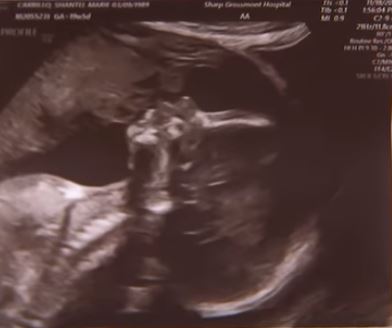

圖片說明:(只供參考、探討)

左邊這張超音波影像讓尚特爾•卡莉蘿(Shantel Carrillo)相信有天使。卡莉蘿說:「這讓我驚呆了!真的是這樣!」當尚特爾懷有第二個小孩時,她在超音波影像中看到已故的父親正在親吻她尚未出生的胎兒(請注意:胎兒的嘴唇似乎也在回應)。右邊的影像看起來就像是一張男人臉的輪廓,他的帽簷正傾向著胎兒。

她將這張超音波影像與另一張相片—她父親查理戴著棒球帽,抱著第一個孫子的合照,進行比對之後,被影像的相似之處震驚了:無論是鼻子、臉頰,尤其是,父親最明顯的特徵—戽斗(下巴形狀像顆小球),更是神似。但她父親已在兩年前因心臟病去世,而父親的生日則與嬰兒大約都同在4月份。